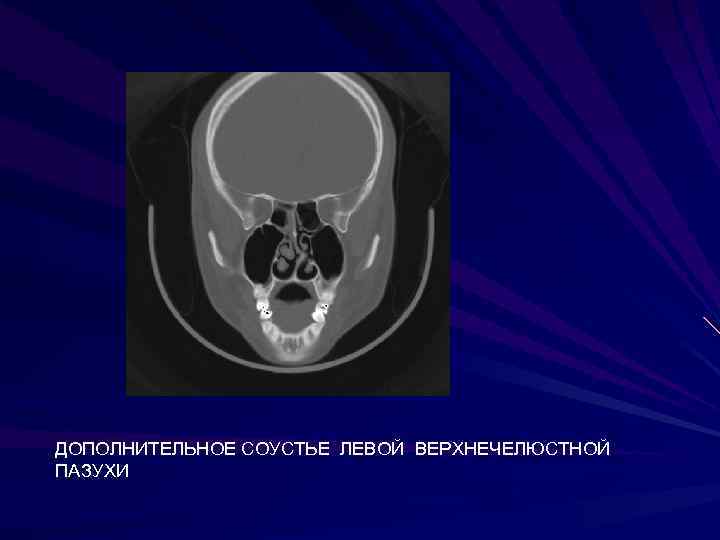

ДОПОЛНИТЕЛЬНОЕ СОУСТЬЕ ЛЕВОЙ ВЕРХНЕЧЕЛЮСТНОЙ ПАЗУХИ ДОПОЛНИТЕЛЬНОЕ СОУСТЬЕ ЛЕВОЙ ВЕРХНЕЧЕЛЮСТНОЙ ПАЗУХИ